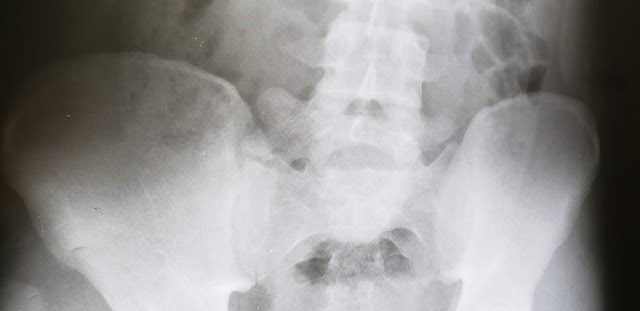

Cleiton passou por exames de rádio x, sendo detectado uma pequena fratura no sacro, na região do quadril. O mesmo terá que usar moletas para recuperação. Eric seguiu para o raio x, porém aparentemente não sofreu fratura exposta.

| Cleiton sofreu fratura no sacro, no quadril. |